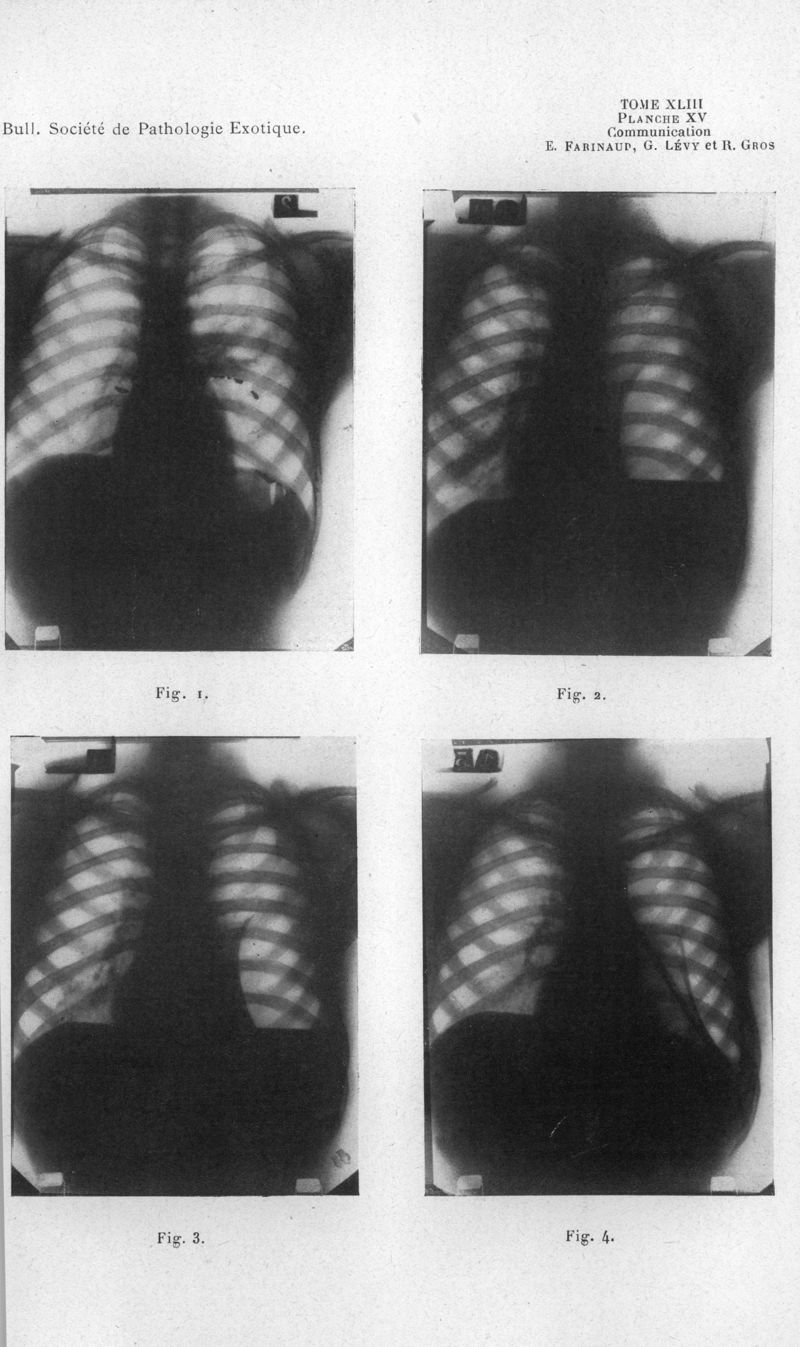

Bulletin de la Société de pathologie exotique et de ses filiales

1950, tome 43. - Paris : Masson, 1950.